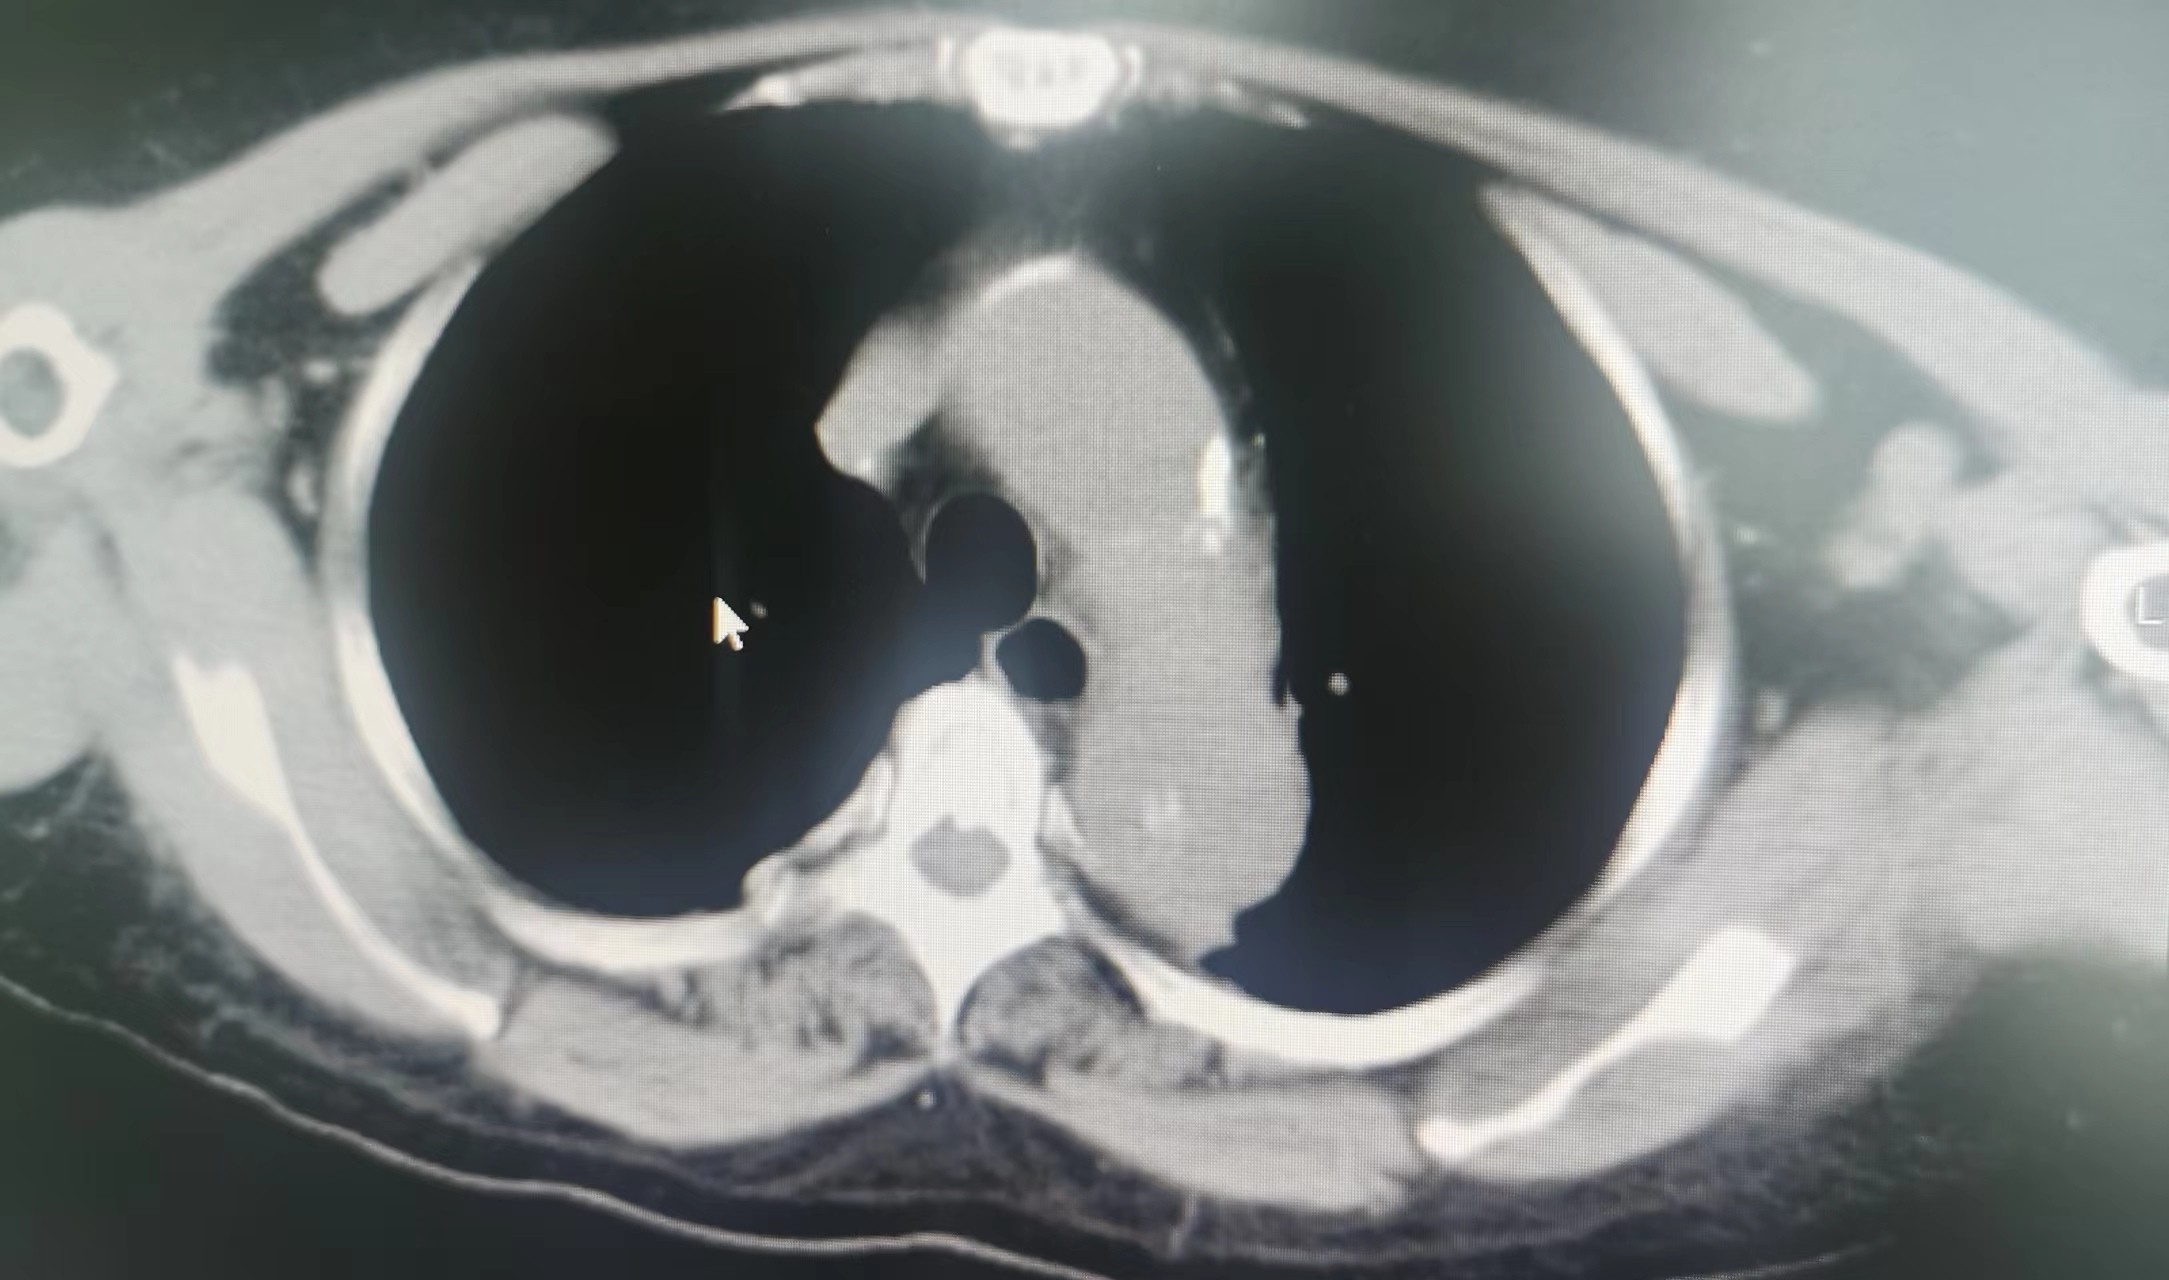

2023年11月,廖阿姨开始出现上腹部不适及胸痛,在外地医院住院治疗,当时查胸部CT考虑为:1.肺纤维化;2.双肺小结节;并经完善其他相关检查后考虑腹痛为:慢性胃炎(未行胃镜检查)。因临近过年,廖阿姨决定回本地过春节,在外地住院治疗10余日后和我院血液净化中心联系透析事宜。2023年12月,廖阿姨在我院透析时仍诉有上腹痛,值班医生经过仔细查体,感觉廖阿姨不像单纯慢性胃炎那么简单。首先,廖阿姨剑突下压痛不明显;其次,廖阿姨腹痛呈阵发性加重,加重时疼痛可累及左侧胸部,严重时胸部疼痛呈撕裂感,这些不像仅有慢性胃炎的症状。我院肾内科主任、主任医师李友河会诊后建议患者住院进一步检查,廖阿姨当日办理了住院。廖阿姨住院期间,肾内科予以相关治疗后其腹痛逐渐缓解,但未完全消失,经李友河主任、主管医生反复沟通和讲解病情后,廖阿姨及其家属终于认识到病情发展的严重性,从原本不愿检查的态度转变为同意完善胸部CT检查。经胸部CT平扫,结果为:1.主动脉夹层可能,建议进一步增强检查;2.右肺、左肺上叶少量慢性炎症;3.主动脉、冠状动脉硬化;4.心包少量积液,左侧胸腔少量积液。

当结果出来后,李友河主任第一时间查看了结果,并马上和患者家属沟通,建议廖阿姨马上行胸部CT增强扫描,同时,我院将立即开通绿色通道,转入我院深度帮扶医院——广东省人民医院进行救治。当晚,廖阿姨胸部CT增强结果提示为主动脉夹层,我院立即派出救护车和医护人员,全程护送廖阿姨至广东省人民医院进一步救治。廖阿姨先后在省人民医院心脏急危重症监护室、心内五科治疗,3日后,省人民医院专家为其行胸主动脉覆膜支架腔内隔绝术+暂时性经静脉起搏器系统的置入等治疗,2024年1月廖阿姨好转出院,并继续预约到本院透析。廖阿姨及家属在省人民医院出院后,十分感激我院及省人民医院的救命之恩,他们认为在省人民深度帮扶我院以来,佛冈县人民医院打出了“省医就在家门口的口号”,不管是佛冈县人民医院的医疗技术,还是医德医风均取得了很大的进步。随后,廖阿姨特地送来了锦旗,感谢全体肾内科医护人员的救命之恩。我院肾内科坚持“以患者为中心”的理念,进一步改善医疗服务,满足患者日常就医需求,为患者提供全周期的诊疗服务,在不断提高诊疗水平的同时,丰富服务内涵建设,改善患者就医体验,为广大群众生命健康保驾护航。科室简介